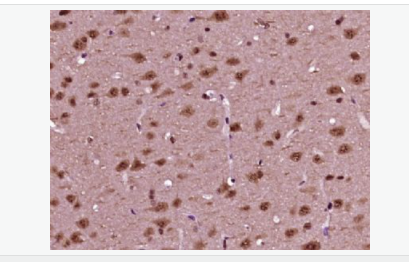

中文名稱磷酸化神經細胞分化因子1抗體

別    名NeuroD1 (phospho S274); p-NeuroD1 (phospho S274); atonal; basic helix loop helix transcription factor; BETA 2; Beta cell E box transactivator 2; BETA2; BHF 1; BHF1; bHLHa3; class A basic helix loop helix protein 3; Class A basic helix-loop-helix protein 3; MODY 6; MODY6; NDF1_HUMAN; NEUROD; NeuroD1; Neurogenic differentiation 1; Neurogenic differentiation factor 1; neurogenic helix loop helix protein NEUROD; NIDDM.

產品應用WB=1:500-2000 ELISA=1:5000-10000 IHC-P=1:100-500 IHC-F=1:100-500 ICC=1:100-500 IF=1:100-500 (石蠟切片需做抗原修復)

細胞定位細胞核 細胞漿

Phosphorylated. In islet cells, phosphorylated on Ser-274 upon glucose stimulation; which may be required for nuclear localization. In activated neurons, phosphorylated on Ser-335; which promotes dendritic growth.